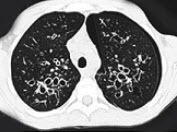

230、单项选择题

女,36岁,咳嗽,咳痰,咯血,反复发作,CT检查如图,应诊断为()

A.双下肺支气管扩张并感染

B.多发性肺囊肿并感染

C.双下肺肺包虫病

D.间质性肺炎

E.肺气肿